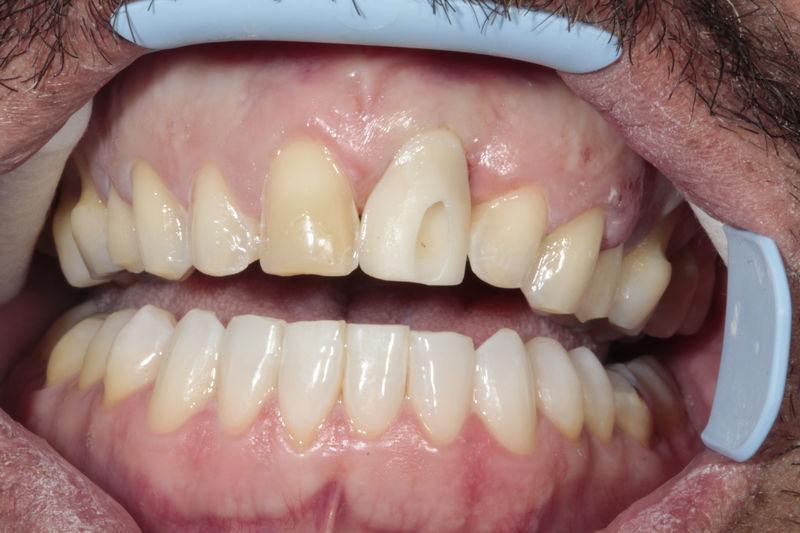

Amplia gama de tratamientos para mejorar la apariencia de la sonrisa, corrigiendo el color, la forma, el tamaño, la alineación y la posición de los dientes. Los procedimientos más comunes y solicitados incluyen el blanqueamiento dental, las carillas y coronas, así como las resinas.

Implante fracasado, extracción, carillas, coronas y prótesis fija.

Implantes, ortodoncia y coronas.

Ortodoncia y coronas.

Cirugía ortognática, implantes, carillas y coronas,